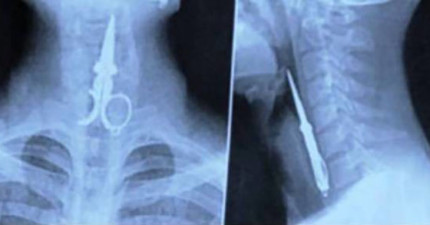

18个连医生都不相信会在人体里发现的奇怪物品。

February 12, 2015

世界